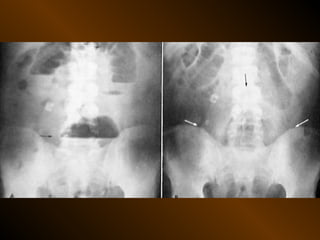

KHÍ TỰ DO

TRONG KHOANG PHÚC MẠC

NGUYÊN NHÂN

thủng tạng rỗng

nguồn gốc xuyên phúc mạc

nguồn gốc trong phúc mạc

10 – 15% thủng tạng rỗng → không thấy hơi tự do ổ bụng